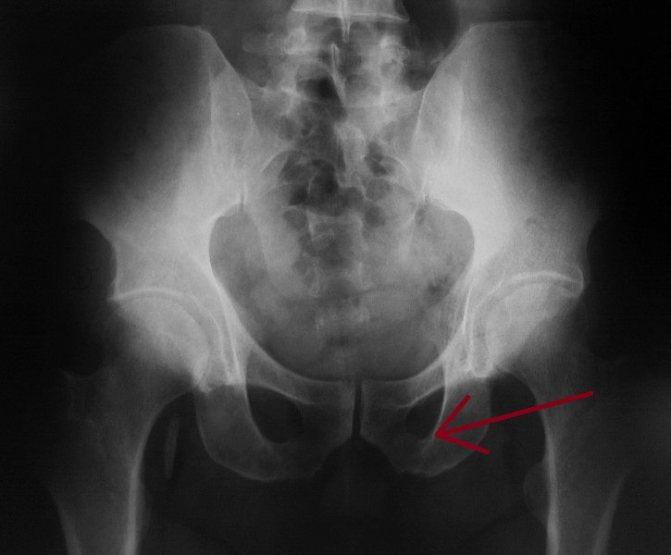

Диагностика

Пострадавший может находиться в бессознательном состоянии после полученного болевого шока. Для того, чтобы уточнить диагноз и начать соответствующее лечение рекомендовано проведение таких исследований:

- Рентгена.

- МРТ.

- Компьютерной томографии.

Для постановки точного диагноза врач должен собрать все детали анамнеза травмы. Пациента или свидетелей опросят относительно того, в какой позе находился пострадавший в процессе падения. После этого врач тщательно осматривает пациента.